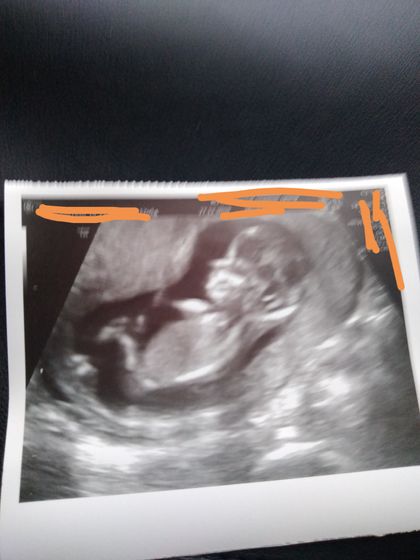

Сегодня делали скрининг. Все хорошо, плод развивается в норме. Кровь сказали будет 9 января. Если что то будет, то пришлют смс, если нет, то ничего не пришлют.

Думаю и анализ крови будет хорошим )) длина кости носика в норме так что уже большой плюсик...))